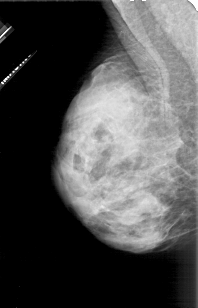

A_1113_1.LEFT_MLO

LEFT_MLO LINES 4606 PIXELS_PER_LINE 2956 BITS_PER_PIXEL 12 RESOLUTION 43.5 NON_OVERLAY